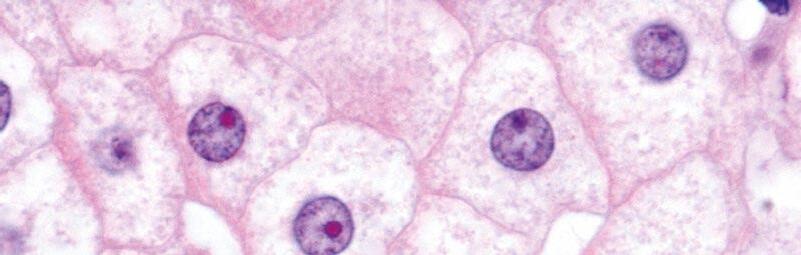

They are secondary metabolites of certain fungi (genera Aspergillus, Penicillium, Fusarium, Alternaria, and Claviceps)[1] and are produced before harvest of grains (fungi as plant pathogens), or during storage (fungi growing saprophytically).

AFs are produced mainly by Aspergillus flavus, A. parasiticus and A. nomius and are detected usually in maize, peanuts and cottonseed.

AFs and, in particular, AFB1 are considered the most potent naturally occurring carcinogens. AFB1 is metabolised predominantly in the liver by a number of cytochrome P450 enzymes, generating several hydroxymetabolites, such as AFM1, AFQ1 and AFP1 and two significantly reactive epoxides, AFB1 exo-8,9-epoxide and AFB1 endo-8,9-epoxide[20-22] .

The exo-epoxide interacts with the guanine part of DNA, resulting in the formation of AFB0-guanine adducts such as AF-N7-Gua which can be used (in urine) as a biomarker of exposure[20,21,23]

Both the endo- and exo-epoxide of AFB1 are toxic and lead to the formation of aflatoxin–albumin (AF-alb) in hepatocytes, which are observable in the sera of exposed animals and humans[20]. These albumin adducts of AFs have been discussed as useful biomarkers of AFs-induced hepatotoxicity[20]

Aspergillus species mainly, and Penicillium species can produce ochratoxins with OTA having major nephrotoxic properties.